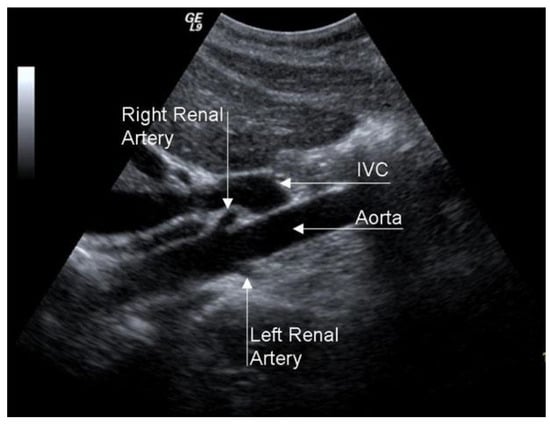

A duplex scan is an excellent examination for RAS screening, even if its efficacy is limited in obese patients or with intestinal meteorism (Figure 14).

Figure 14. Duplex scan of the renal arteries (long axis view). IVC, inferior vena cava.